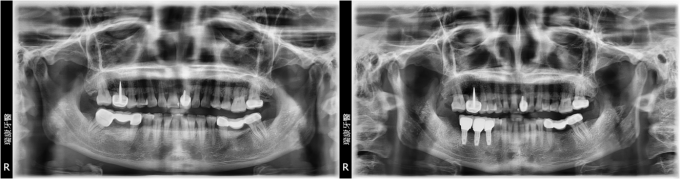

病患王先生,57年次,上班族

- 主訴:想要重建右下缺牙區

- 治療計劃: 安排精密3D電腦斷層評估後,進行人工植牙, 三個月後接出假牙基座印模製作正式假牙!

實例照片僅為資訊介紹及分享,效果可能因個人體質及保養方式不同而有所差異。